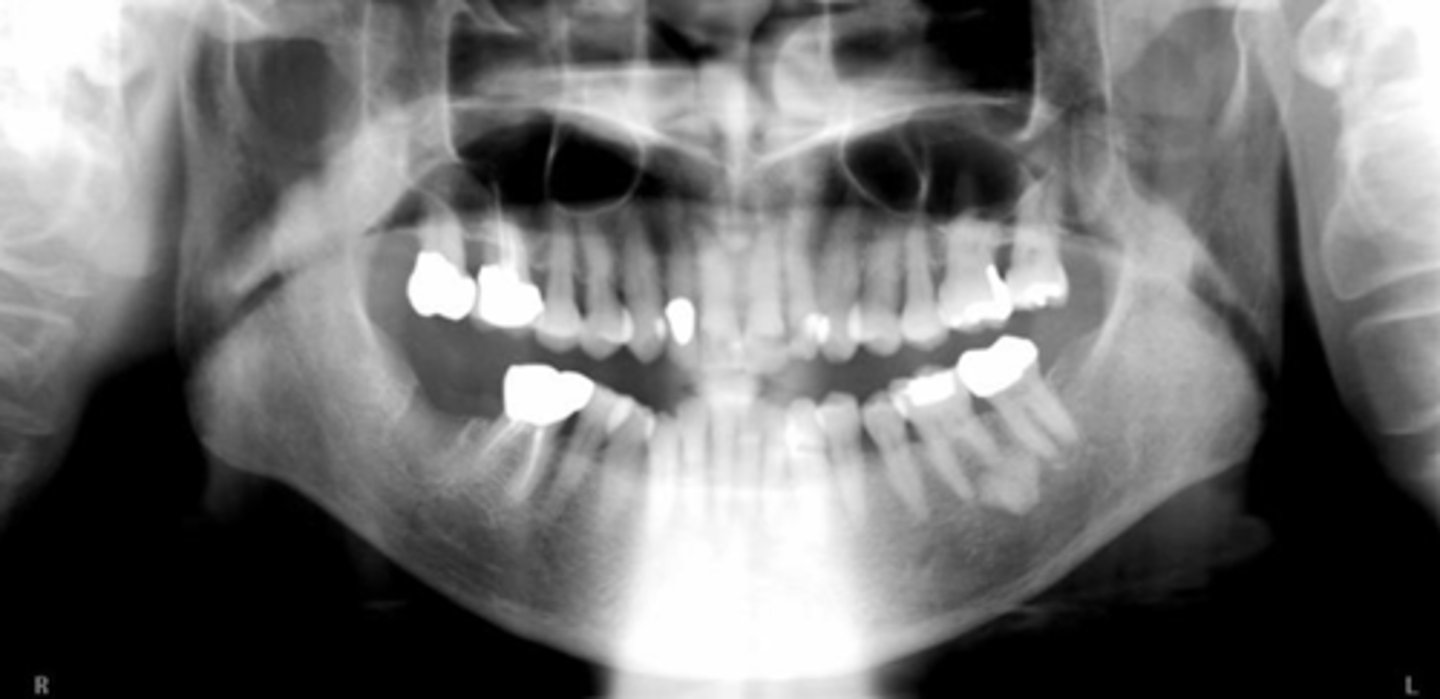

B) ghost

The white arrows represent the ___ hard palate

A) real

The black arrows represent the ___ hard palate

B) ghost left mandible

The black triangles represent the ___

A) real left mandible

C) real right mandible

D) ghost right mandible